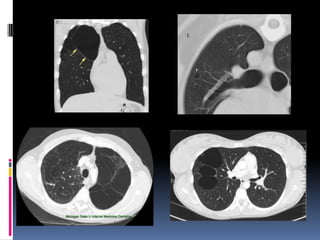

BULLA  Un espacioaéreo de más de 1 cm-por lo general de varios cm de diámetro, bien delimitada por una pared delgada que no es mayor de 1 mm de espesor. Una bulla normalmente esta acompañado por enfisema y cambios en el pulmón adyacente. Rx y TAC bulla  aparece como una lucidez redondeada focal o área de disminución de la atenuación.  Bullas múltiple están asociados con otro sg de enfisema pulmonar (centrolobulillary paraseptal).

ENFISEMA BULLOSO  enfisemabulloso es la destrucción del parénquima pulmonar, generalmente en un fondo de paraseptal o enfisema panacinar.